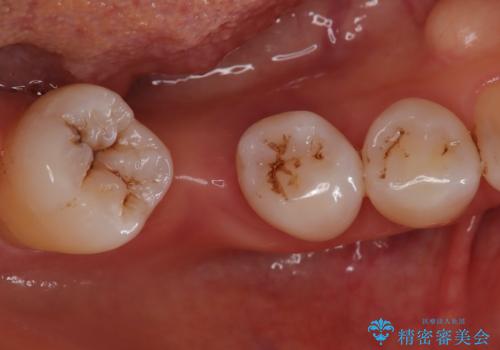

- 歯がぐらぐらしてきて怖いとのことで、当院に来院された患者様です。

できる限り歯が保存できるように治療したいとのことでエムドゲインを用いた再生治療を行っています。

歯周病の原因に咬合干渉が疑われる為、ワイヤーにて固定を行っています。